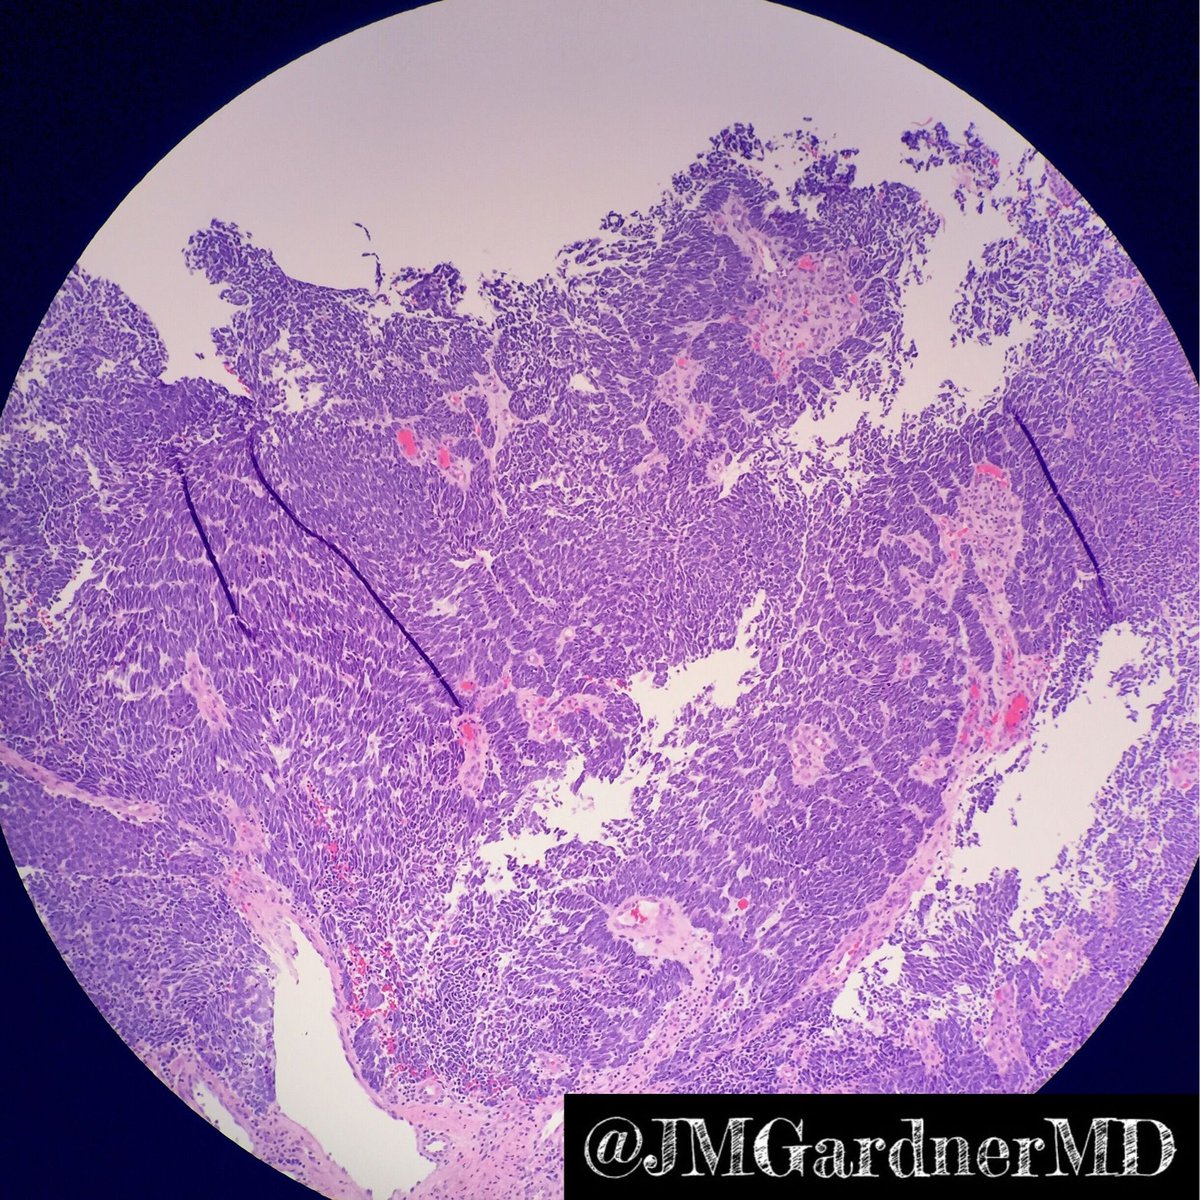

60 yo man with 2 cm breast mass. One of the BEST examples ever! Can you make diagnosis from one pic, or is it #TooCloseToDiagnose? Digital slide: kikoxp.com/posts/4600. Answer ✅ youtube.com/watch?v=eLmPGd… #pathologists #pathology #pathTwitter #BSTpath #breastpath

60 yo man with 2 cm breast mass. One of the BEST examples ever!

Can you make diagnosis from one pic, or is it #TooCloseToDiagnose?

Digital slide: kikoxp.com/posts/4600.

Answer ✅ youtube.com/watch?v=eLmPGd…

#pathologists #pathology #pathTwitter #BSTpath #breastpath